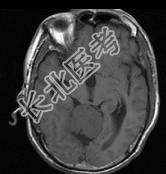

- 单项选择题男,61岁, 头晕头痛伴行走不稳1月余,请根据所提供图像, 诊断最有可能是 ( )

A、转移瘤

B、胶质瘤

C、淋巴瘤

D、髓母细胞瘤

E、(天幕切迹缘)脑膜瘤